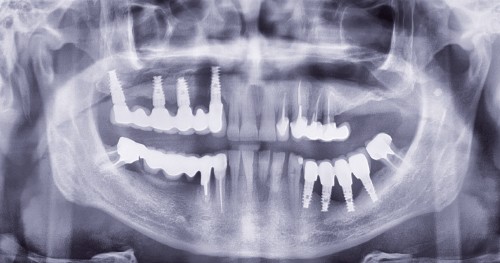

Question 1. Le carcinome épidermoïde, l’épulis et le granulome pyogénique peuvent a priori être évoqués tous les trois. La petite taille et le siège classiquement labial de l’hyperplasie endothéliale intravasculaire [4] permettent d’écarter ce diagnostic. Dans tous les cas, seul l’examen anatomopathologique permet d’étiqueter la lésion.

Le carcinome épidermoïde doit être évoqué du fait des caractéristiques de la lésion, de l’adénopathie sous-mandibulaire et du passé tabagique du patient.

L’épulis inflammatoire, pseudotumeur inflammatoire chronique, se développe généralement sur la gencive marginale ou sur une papille interdentaire. La lésion est habituellement sessile et mesure en moyenne 5 à 10 mm de diamètre. Il est indolore, érythémateux et rarement ulcéré. L’origine traumatique de l’épulis peut correspondre au cas présenté (espaces papillaires insuffisants).

Le granulome pyogénique (syn. botryomycome, hémangiome capillaire lobulé) est une lésion bénigne d’origine vasculaire [2]. Il siège sur la peau et, surtout, sur les muqueuses, en particulier les lèvres, les gencives, les joues et la langue. La lésion en bouche peut être unique ou multiple. Elle se présente comme un nodule saillant, souvent sessile, rarement pédiculé. La lésion est…